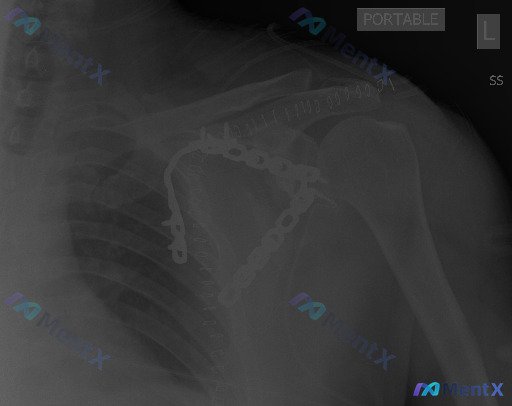

整理到一张左肩部正位X光片的读片资料,先不说最终结论,大家第一眼扫下来,会先抓住哪个核心异常? 目前先给基础的客观描述方向: - 骨性结构里能看到高密度的金属影 - 肱骨头轮廓是光滑的 - 关节间隙看起来没有明显的狭窄或增宽 可以先聊聊第一步阅片思路。